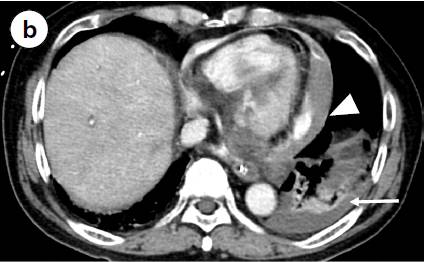

a 心电图显示Ⅱ、Ⅲ、aVF导联出现ST段抬高及Q波。 b 轴位CT扫描图像显示造影剂渗漏到心包、纵隔(三角形箭头)以及左侧胸腔的血性积液中(长箭头)。冠状位(c)和矢状位(d)CT重建显示造影剂从左心室向心包渗漏(长箭头)和右心室壁相对比的低密度影(三角形箭头)。